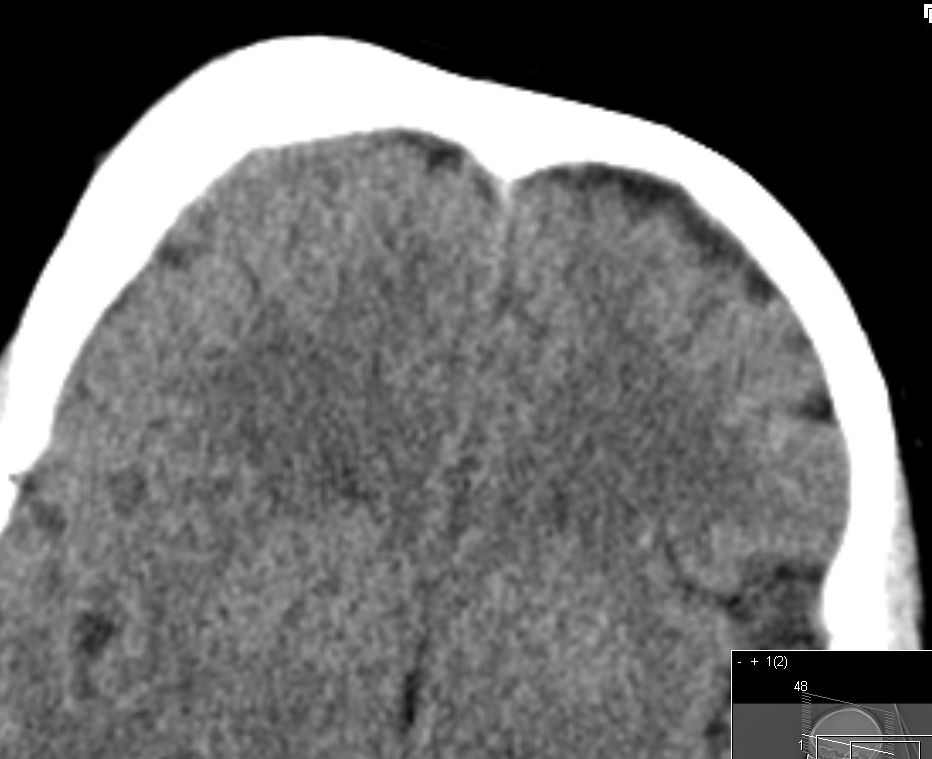

| 72-jährige Patientin mit Teilparese des rechten Beins, passageren Sprachstörungen und Krampfanfall vor 6 Monaten. Postoperative Histologie: Meningeom Grad 1 | CT vor KM-Gabe . |